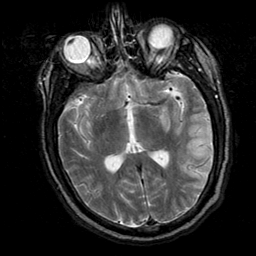

Subacute Stroke, overlay -- Slice #12

[Home][Help][Clinical] Slice 12